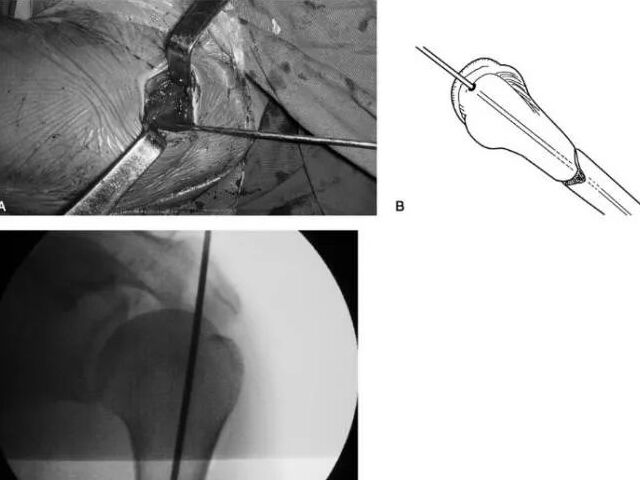

AO Standardoperation: Skruvfästning för förskjutna frakturer av talus-halsen

2025/12/31AnatomiBlodförsörjningen till talus är allvarligt komprometterad vid fraktur-luxationer. Arteria tibialis posterior avgivar grenar mediaalt, arteria dorsalis pedis anterioralt och peronea arterien lateralt. Dessa kärl anastomosera via en...